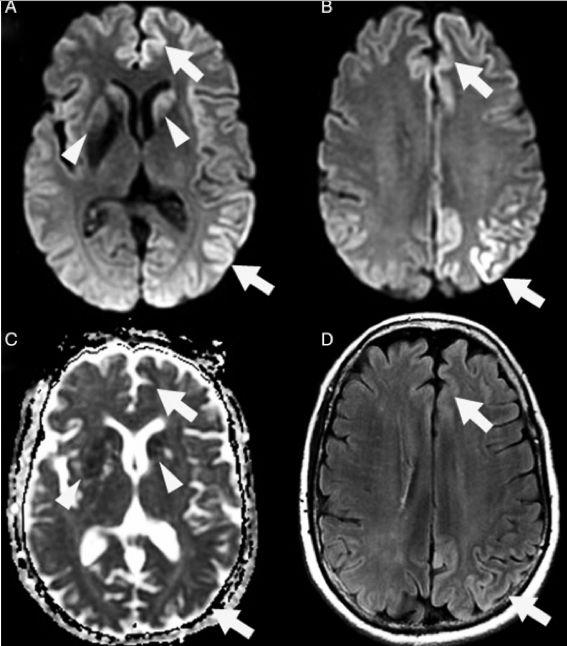

经现代医学研究证明,“朊病毒”可以造成人畜共患疾病,其主要危害目标是以中枢神经,引发神经系统变性以及蛋白聚集,现在发现的主要病征包括动物患上的“疯牛病”,以及人类患上的克-雅综合征、库鲁病、格斯特曼综合征、致死性家庭性失眠症等等,其共同的症状就是患病者的脑部组织出现海绵状的空洞,同时伴有抽搐、痴呆、行为失调等,死亡率非常高。